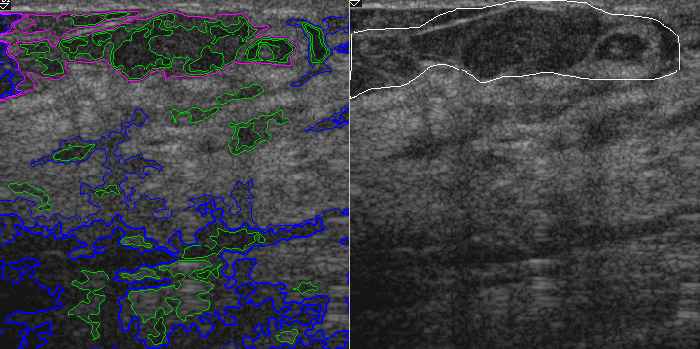

Computer-Aided Detection in Ultrasound: The current method of detection and analysis of suspicious areas is based on manual inspection of the acquired images. It is subjective and error-prone. Our technology not only can view and display comprehensively (enhanced view on the left and traditional view on the right), but can detect, quantify and search images too.

Quantification and Scoring of suspicious area: Previously detected suspicious areas are automatically detected and quantified. They can then be compared to one marked by radiologist (accuracy test) and numerically scored to the level of suspicion.